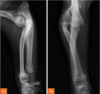

Fractures can be either..

primary or secondary.

Also, complete or incomplete. (periosteum can be intact with fracture line otherwise).

Left image: gunshot caused fracture.

Right image: osteosarcoma caused fracture.

Q

A

incomplete fractures

22

identify left to right

left to right:

Transverse fracture

Oblique fracture

Spiral fracture